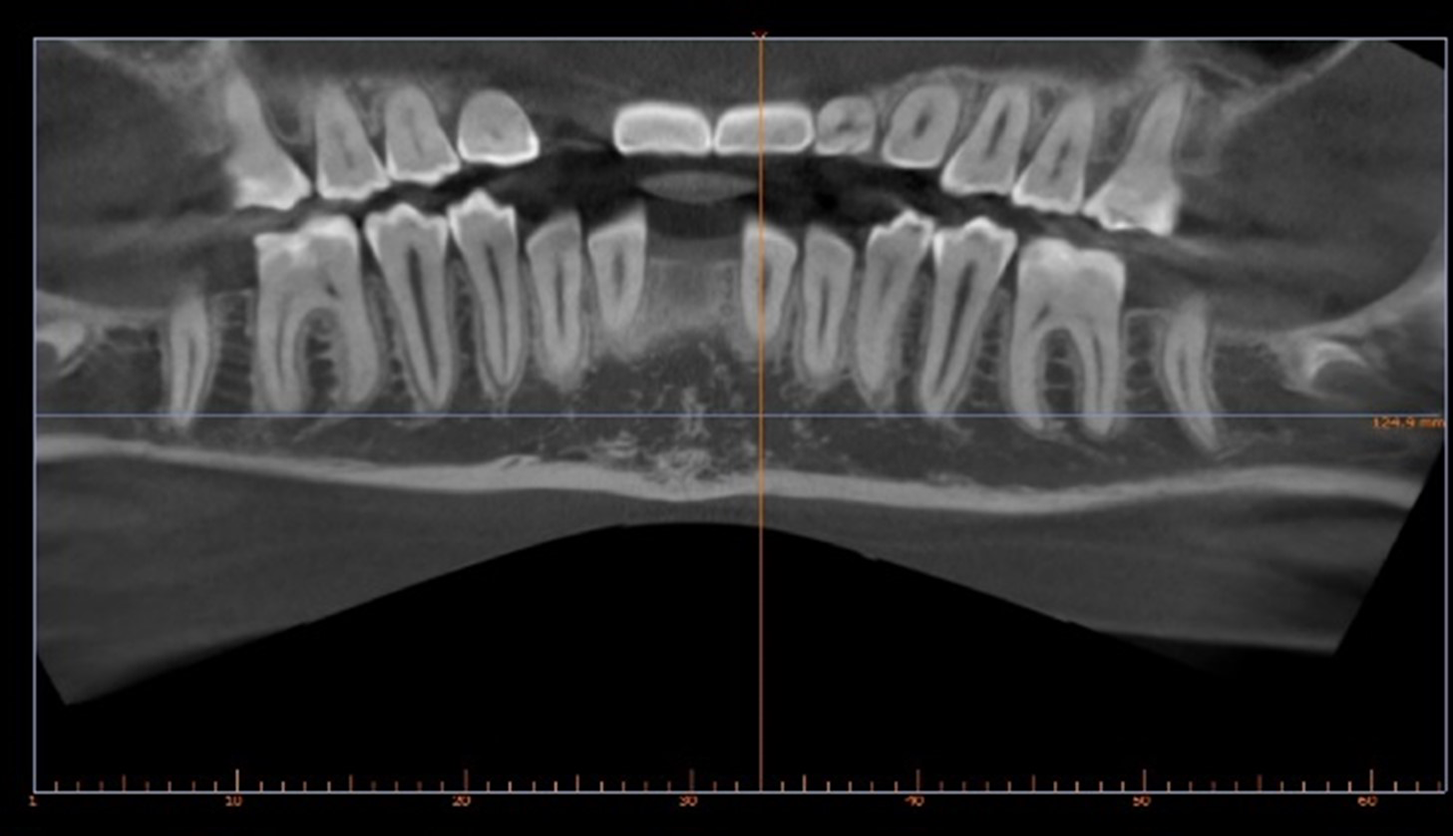

Two finishing stages were carried out after CBCT

18 aligners then 9 aligners (TruGen XR™)